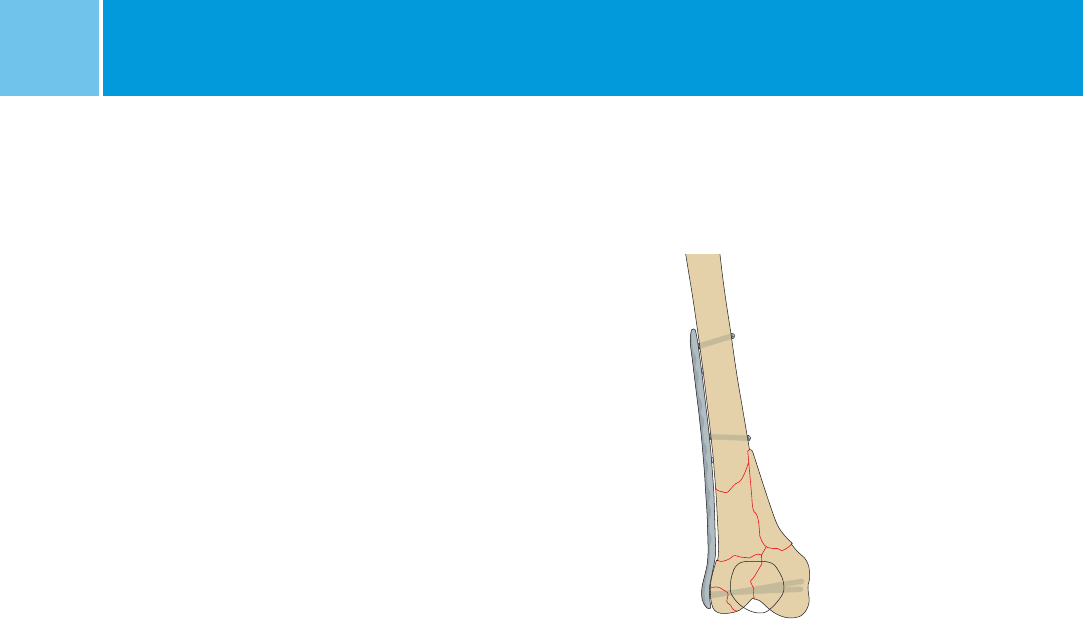

Insertion of the NCB Plate

Insert the plate between the vastus

lateralis muscle and the periosteum.

Keep the proximal end in continous

contact with the bone surface during

insertion. Place the distal end of the

plate against the lateral condyle.

Note: The plate is anatomically shaped

and does reach far distally close to the

cartilage – bone interface.